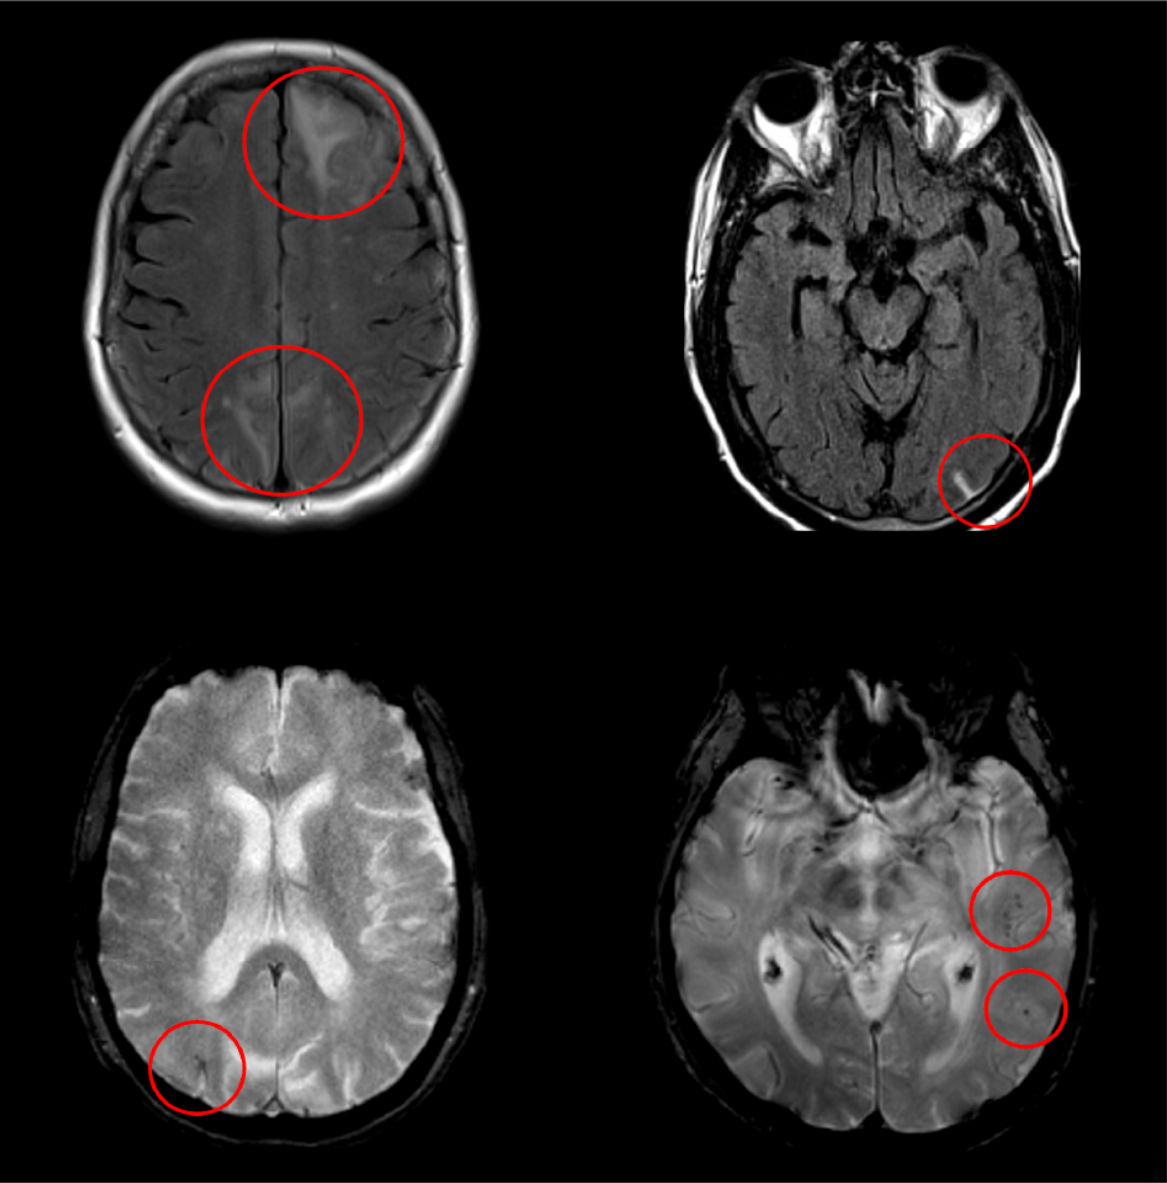

ARIA presents as edema/effusion (ARIA-E) and hemosiderin deposition due to microhemorrhage, superficial siderosis, or intracerebral hemorrhage (ARIA-H). ARIA-H, and less commonly ARIA-E, can occur spontaneously in patients with Alzheimer’s disease. It is thought to be related to underlying cerebral amyloid angiopathy (CAA). The risk of ARIA is increased with the use of monoclonal antibodies that remove amyloid plaques in patients with Alzheimer’s disease.

Magnetic resonance imaging (MRI) is used to monitor and diagnose ARIA. The occurrence of characteristic amyloid-related MRI signal changes requires careful consideration by the treating neurologist and radiologist. ARIA is often asymptomatic and usually resolves without intervention or treatment modification. When intervention or treatment modification is required, ARIA and any associated symptoms usually resolve, but serious events can occur.